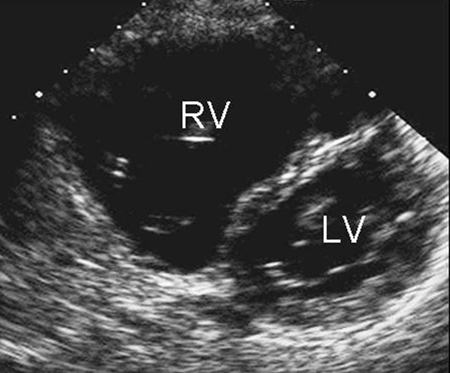

Imagem de ecocardiografia do eixo paraesternal curto revelando um aumento ventricular direito em um paciente com defeito do septo atrial (DSA). (VD) ventrículo direito; (VE) ventrículo esquerdo

Imagem cedida por Patrick W. O'Leary, MD